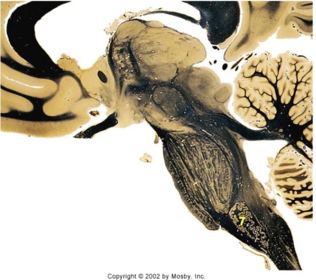

| Head of caudate | |

| Anterior commissure | |

| Thalamus | |

| Substantia nigra | |

| Optic tract | |

| Dentate nucleus | |

| Pons | |

| Longitudinal pontine fibers | |

| Uncus | |

| Superior cerebellar peduncle | |

| Red nucleus | |

| Corticospinal tract (dark) | |

| Pontine nuclei (pale) | |

| Transverse pontine fibers (dark) | |

| Inferior olive | |

| CTT | |

| Medial lemniscus | |

| Nucleus cuneatus | |

| Superior colliculus | |

| Inferior colliculus | |

| Optic nerve | |

| Cerebellum | |

| 4th ventricle | |